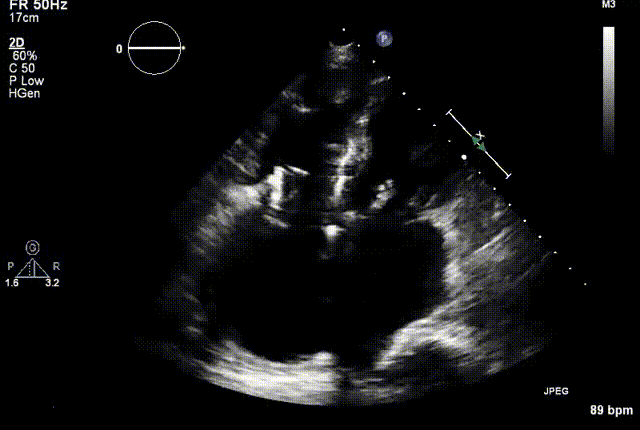

两例患者是都是外科手术高危的极重度三尖瓣反流的老年女性,反复下肢水肿、腹胀、纳差,活动耐力减退。一例患者风湿性心脏病,二尖瓣生物瓣置换术后,房颤,心超显示三尖瓣极重度反流(最大反流宽度15mm);另一例患者房颤,心超示三尖瓣极重度反流(最大流宽度23mm)。

结合术前CT评估结果,葛均波院士团队最终决定选用LuX-Valve Plus 50mm和55mm两种型号的瓣膜,并于2021年11月30日顺利完成LuX-Valve Plus经血管三尖瓣置换术,手术室即刻拔除气管插管,术后第二天转出心内科监护室,下床活动。术后患者三尖瓣反流症状得到显著改善,复查心超结果显示人工三尖瓣瓣膜支架固定稳定,瓣叶关闭形态未见异常,未见明显反流。

复查心超图

在本次救治性临床研究中,治疗的两例患者病因不同解剖结构复杂,均为极重度三尖瓣反流,手术最终都顺利植入了LuX-Valve Plus三尖瓣人工瓣膜。术后超声显示瓣膜支架固定稳定,反流症状显著改善,取得了良好临床治疗效果。